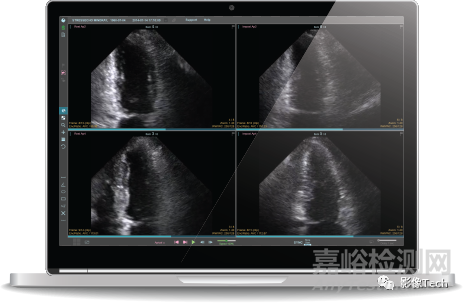

AI助力超聲心動圖識別主動脈瓣狹窄

2023年6月15日,兩家醫(yī)療軟件技術(shù)公司Core Sound Imaging公司和Echo IQ公司宣布達成合作協(xié)議,將為超聲心動圖用戶提供一種基于人工智能(AI)的主動脈瓣狹窄識別技術(shù),從而提高診斷的準確性和效率。

主動脈瓣狹窄是老年人最常見的心臟瓣膜疾病之一,如果不能及時診斷和治療,將面臨高死亡率?;诖?,Studycast系統(tǒng)的開發(fā)商Core Sound Imaging公司與EchoSolv的開發(fā)商Echo IQ公司達成合作協(xié)議,使Studycast用戶能夠利用EchoSolv的AI技術(shù)識別主動脈瓣狹窄。

Core Sound Imaging公司是Studycast系統(tǒng)的開發(fā)商,該系統(tǒng)是一種云端超聲心動圖解決方案,可以實現(xiàn)影像的存儲、傳輸和分析報告。Echo IQ公司是EchoSolv的開發(fā)商,該軟件是一種AI決策支持工具,可以使用常規(guī)超聲心動圖來識別有死亡風險的主動脈瓣狹窄患者。雙方的合作使Studycast用戶能夠方便地將選定的超聲心動圖像傳送到EchoSolv,并將分析結(jié)果納入報告中。